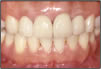

【審美歯科治療】

白い物(セラミック)を用いているだけが審美歯科治療ではありません。審美歯科治療とは歯周組織が健康で機能的にも問題がなく、見た目においても調和がとれ、長期的に安定した治療のことをいいます。

症例1審美歯科治療前症例2審美歯科治療後

▲症例1 治療前▲症例1 治療後